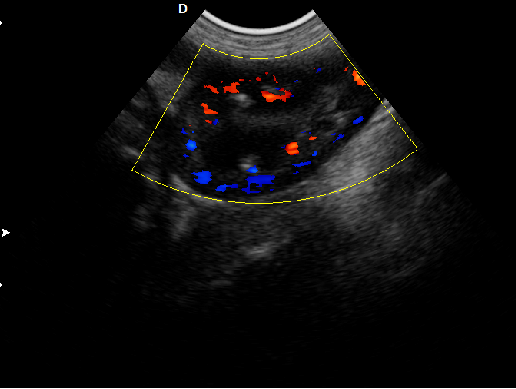

P5-VET便攜獸用彩超機頸動脈檢查圖

頸動脈血流:

頸動脈彩超是診斷、評估頸動脈壁病變的有效手段之一,在動脈粥樣硬化的流行病學調查和對動脈粥樣硬化預防、治療試驗的有效性評價中起著關鍵作用。

頸動脈彩超不僅能清晰顯示血管內中膜是否增厚、有無斑塊形成、斑塊形成的部位、大小、是否有血管狹窄及狹窄程度、有無閉塞等詳細情況, 并能進行準確的測量及定位,還能對檢測動脈的血流動力學結果進行分析。